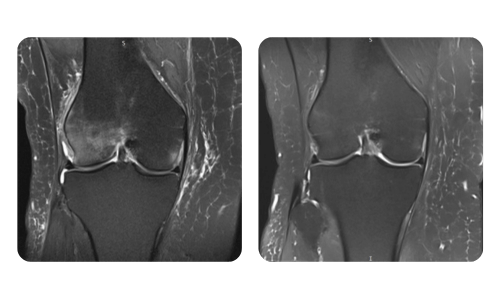

Progresul pacienților noștri, măsurat înainte și după terapia hiperbară, reflectă eficiența și impactul pozitiv al tratamentului. Descoperă rezultate documentate ale terapiei hiperbare la clinica Hyperbarium Oradea, bazate pe evaluări clinice și date obiective care evidențiază îmbunătățiri semnificative în diverse afecțiuni.